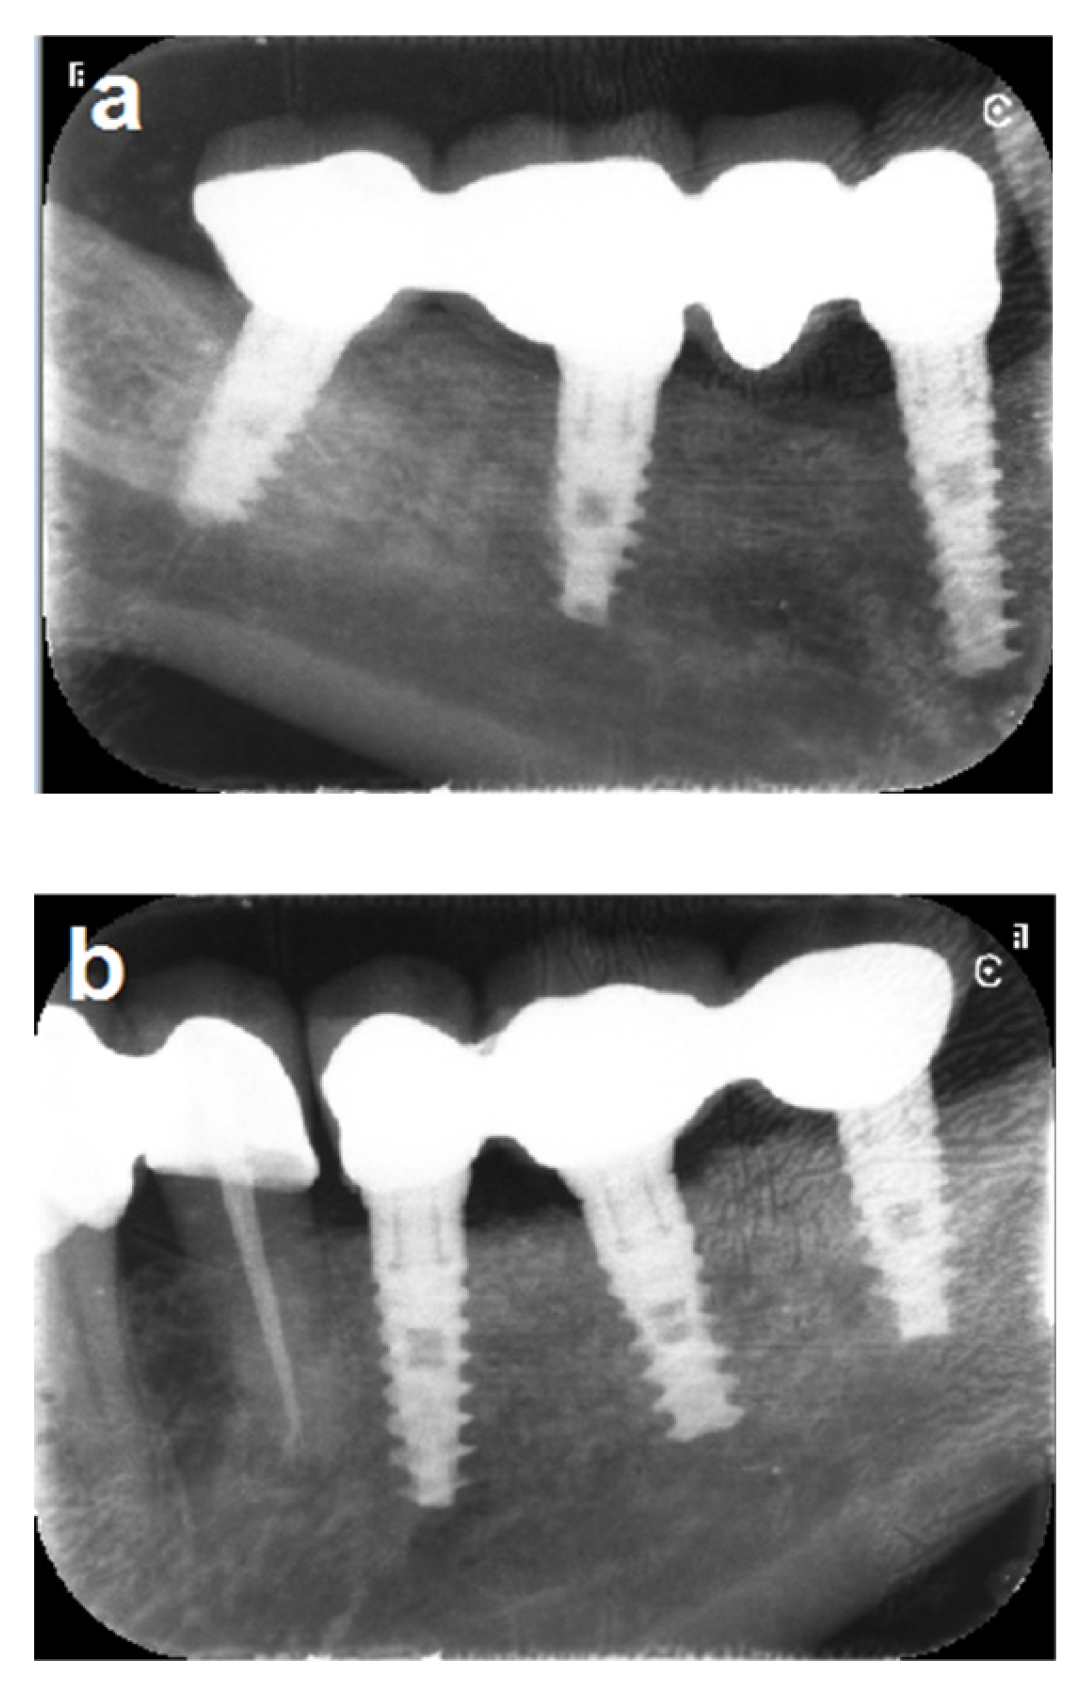

In one patient (Patient No. 19), one of three implants at the left mandibular site failed after 10 years. The failed implant was removed and replaced four months after particulate bone grafting, leading to successful fixed prosthetic rehabilitation with the remaining two implants. The same patient exhibited a 3 mm marginal bone loss on the right side (Figure 9). Another patient (Patient No. 6) experienced severe bone loss affecting the distal implant, along with a fracture of the mesial implant, after 13 years (Figure 10).

Figure 9.

(a,b) Ten-year follow-up periapical x-rays reveal severe bone loss involving the distal implant on the left side, along with 3 mm of marginal bone loss at the middle implant on the right side. (c–e) The images demonstrate stable bone grafts despite the severe marginal bone loss at the distal implant on the left side.

Five implants in five patients exhibited a 3 mm bone loss; however, they remained asymptomatic and were successfully maintained with regular professional cleaning (e.g., Patient No. 7, Figure 11a, and patient No. 18, Figure 11b).

Figure 11.

(a) A panoramic x-ray taken 13 years after implant loading demonstrates stable outcomes across five implants, though the middle implant on the right side exhibits 3 mm marginal bone loss. (b) A panoramic x-ray taken 11.5 years after implant loading shows stable outcomes for five implants, with 3 mm marginal bone loss affecting the distal implant on the right side.